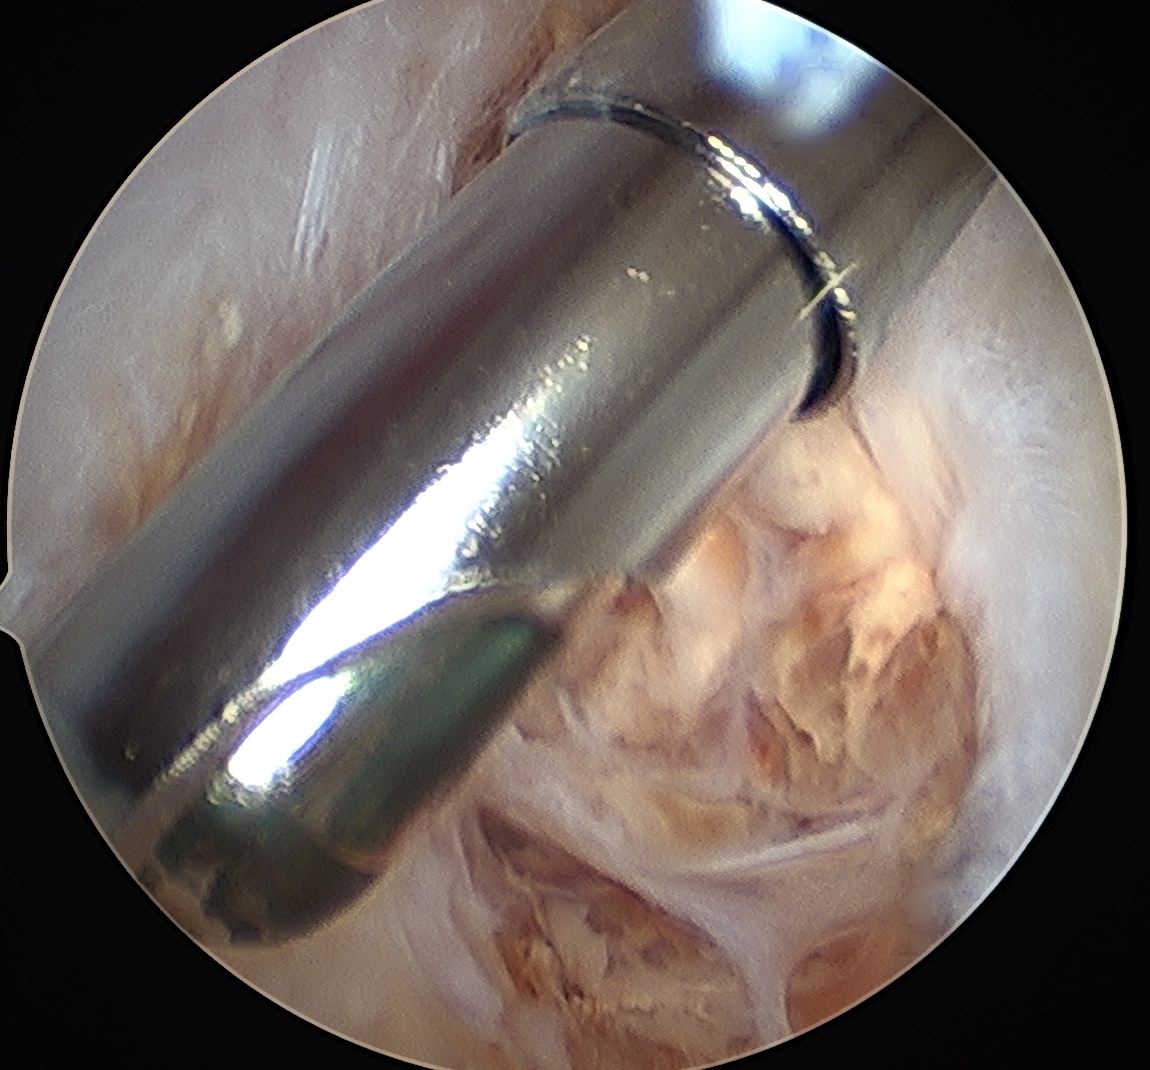

Knee

Arthroscopic synovectomy

Anterior

- suprapatella

- medial and lateral gutters

- ACL / PCL

Posterior compartments

- posteromedial / posterolateral

- transeptal portal